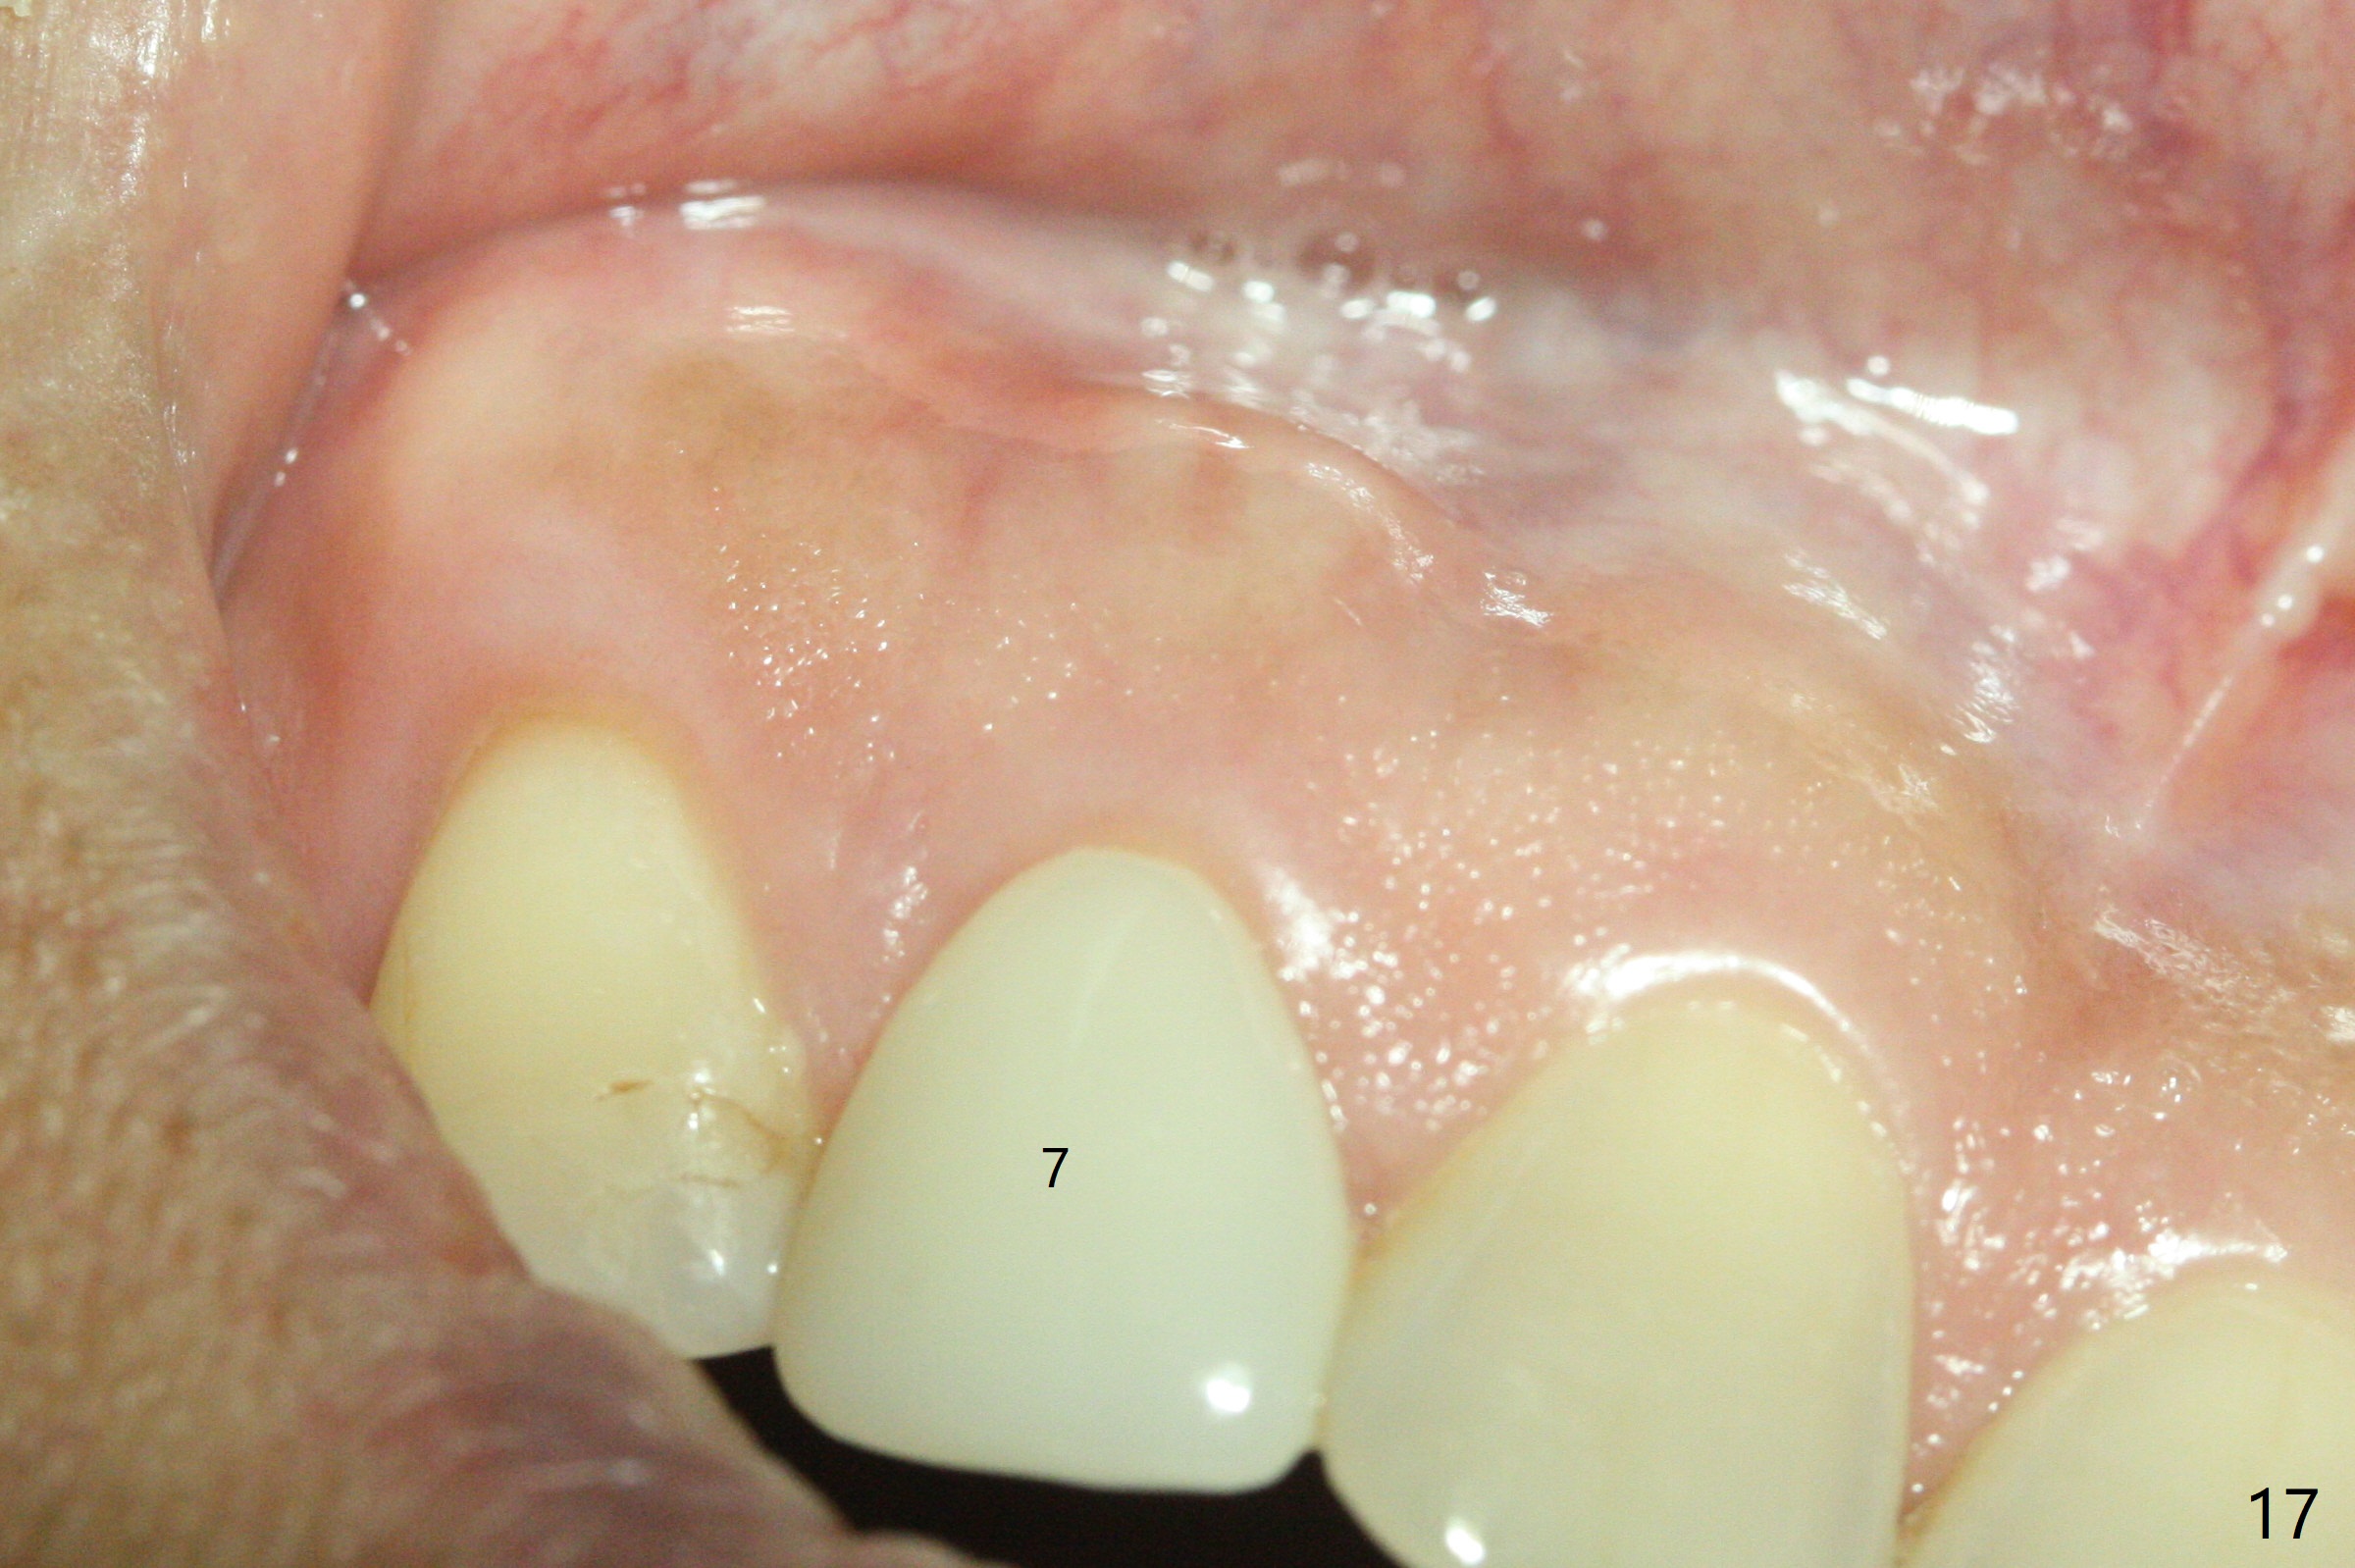

A 49-year-old lady has failed endo on the upper left lateral incisor (Fig.1,2). A gutta percha inserted to the buccal fistula (Fig.1 >) shows a mesial defect (Fig.2<). There is a large buccal apical defect, corresponding to the lesion shown in Fig.2 *, when the affected tooth is extracted. After thorough debridement and Clindamycin soaking, osteotomy is initiated in the palatal wall of the socket. Demineralized freeze dry cancellous bone graft is placed in the buccal defect. A 4x20 mm gingiva-level tapered implant is placed with insertion torque 50 Ncm (Fig.3). A 3x5 mm 20 ° offset abutment is inserted and cemented (Fig.4,5). A retentive groove is prepared on the abutment and the underlying implant; chamfer margin placed on the implant (Fig.4,5). A provisional is fabricated and cemented temporarily (Fig.6,7). Excess cement is removed, followed by removal of gingival retraction cord. There is no contact in centric and non-centric occlusion.

Within one week, the infection resolves (Fig.8,9).

The gingival architecture around the immediate provisional is normal 5 months postop (Fig.10,12). To increase cosmetics for the definitive restoration, the abutment length is reduced (compare arrowheads in Fig.11 to 12).